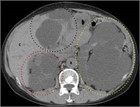

1. 片側の腰背部痛や側腹部痛では水腎症を念頭に置き、まず超音波検査を行い、尿路閉塞の位置と原因を同定するには単純CTを撮影する。